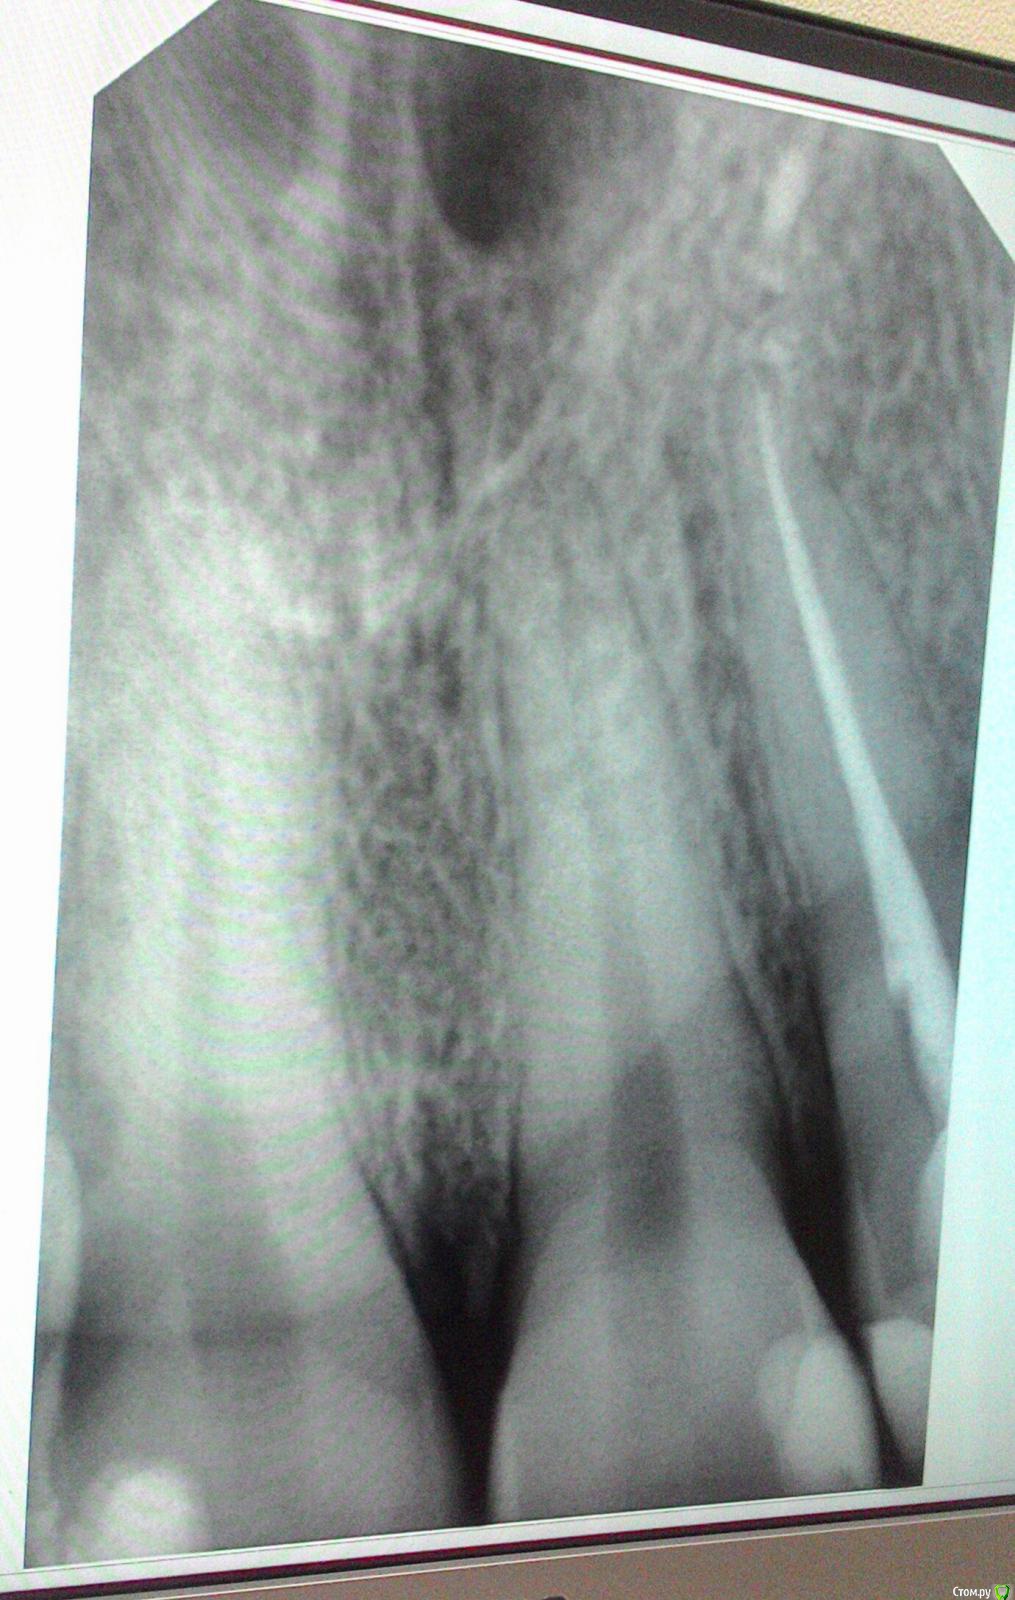

anaG2011 Опубликовано 2 июля, 2018 Поделиться Опубликовано 2 июля, 2018 (изменено) Здравствуйте, уважаемые врачи!Скажите, пожалуйста, нужно ли лечить 11 зуб (центральный правый резец - на фото он слева)? Стоит пломба 2001г. на небной поверхности (сзади). Зуб не беспокоит. Была на осмотре у двух врачей по поводу 11 зуба:1 мнение: Пломба нормальная, если и есть вторичный кариес, то он минимален (даже больше похоже на пигментацию).Рекомендует пока наблюдение 6 месяцев.2 мнение: однозначно лечить сейчас, пока процесс не дошел до пульпы. 22 зуб (левый боковой резец) депульпирован в 2001г. Зуб не беспокоит.12 зуб (правый боковой резец) пломба 2001г. Зуб не беспокоит. Буду благодарна за ваши рекомендации. Изменено 2 июля, 2018 пользователем anaG2011 Ссылка на комментарий

anaG2011 Опубликовано 2 июля, 2018 Автор Поделиться Опубликовано 2 июля, 2018 Добрый вечер !Я не совсем поняла Ваш ответ. Уточню: 12 зуба (правого бокового резца) на снимке нет.11 зуб на снимке расположен слева, затем 21 и самый правый на снимке 22 (депульпирован). Эти зубы лечила в 2001г. Они меня не беспокоят.Хочу понять, есть ли показания лечить. Сначала была в платной стоматологии (мнение 2) - сказали лечить сейчас.Потом в бесплатной городской поликлинике (мнение 1) - пломбы нормальные, наблюдаем полгода. Буду признательна, если Вы поясните Ваше мнение. Спасибо Ссылка на комментарий

anaG2011 Опубликовано 5 июля, 2018 Автор Поделиться Опубликовано 5 июля, 2018 (изменено) Здравствуйте! Дополню вопрос более четкими прицельными рентгеновскими снимками. центральные резцы и 22 зуб:https://c.radikal.ru/c35/1807/59/867599037145.jpg 12 зуб и частично 11 зуб:https://d.radikal.ru/d26/1807/85/5ca9d97b2ed0.jpg Буду благодарна за рекомендации. Изменено 5 июля, 2018 пользователем anaG2011 Ссылка на комментарий

DmitrySH Опубликовано 5 июля, 2018 Поделиться Опубликовано 5 июля, 2018 12, 11, 22 Есть дефекты пломб, лучше переделать. Ссылка на комментарий